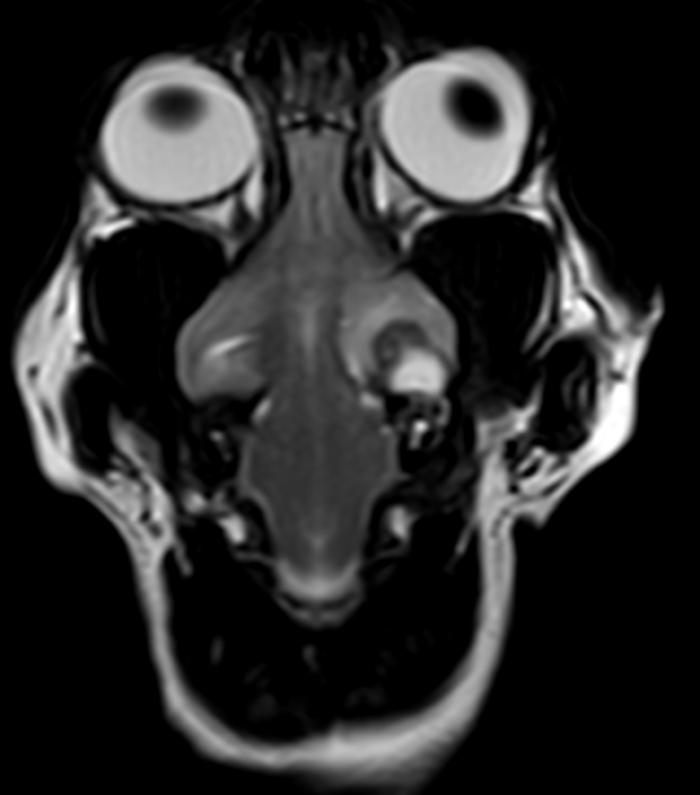

Rinoscopia anterógrada y retrógrada (día 6), con acceso a través de los ollares (acceso retrógrado) y a través de cavidad oral y nasofaringe (acceso anterógrado) con obtención de moco profundo para su cultivo bacteriano, sin observarse anomalías morfológicas (Figura 2), y otoscopia con miringotomía para el drenaje de contenido purulento y toma de muestra para cultivo bacteriano. Las muestras se envían al laboratorio de referencia.

Rinoscopia anterógrada y retrógrada (día 25): se realiza ante la persistencia de secreción nasal bilateral tras antibioterapia, observándose eritema y secreción mucopurulenta y la presencia de un pólipo nasal en la cavidad nasal izquierda (Figura 5A-B), cuyo estudio histopatológico revela una lesión de tipo inflamatorio linfoplasmocitario. La fístula oronasal se ha resuelto completamente. Se observan lesiones líticas en cornetes nasales y endoturbinados.